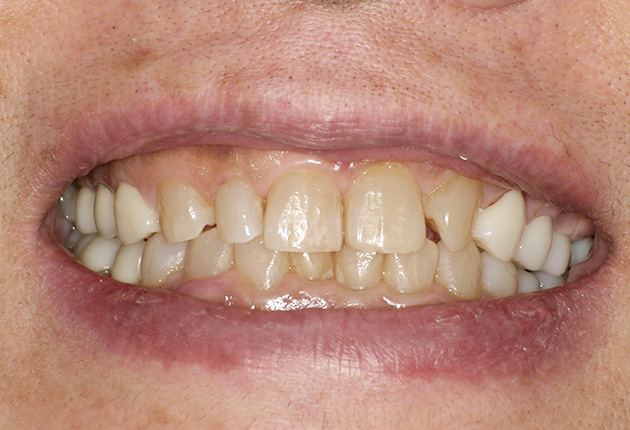

よく噛めず笑うと銀歯が目立つので気にされていました。

90分の治療で銀歯の状態からキレイな状態になります。噛み合わせの調整や審美面も使用しながら合わせます。

良く噛めて安心と、ご満足いただき大変嬉しく思います。笑顔も一層素敵になりました。